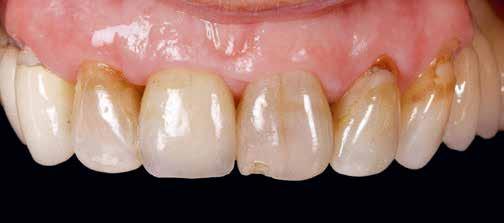

Manapság a minket felkereső és kezelési megoldások után érdeklődő páciensek többsége alkalmas az implantátummal történő rehabilitációra. Ennek oka elsősorban a jelenleg elérhető implantátumtípusok formai kialakításának fejlődésében rejlik, amellyel bármely klinikai szituációhoz alkalmazkodni tudunk rövidebb vagy kisebb átmérőjű implantátumokkal; illetve a regeneratív eljárások, amelyek olykor elkerülhetetlenek, szintén hatalmas fejlődésen mentek keresztül.1,2

Az extra rövid implantátumok alkalmazása mind az alsó, mind a felső állcsont vertikális defektusainál jól kiszámíthatóan alkalmazhatók, a jelenlegi adatok szerint a sikeresség 86,7–100% között mozog.3,4 Vertikális defektusoknál a fő problémát az okozza, hogy a csonthiány miatt az implantátumok és az azokra készülő fogpótlás egymáshoz viszonyított aránya rendkívül előnytelen. A protetikai tér nagy, és a felépítmény–implantátum arány gyakran meghaladja a 2:1 értéket. Ha tanulmányozzuk az erők lehetséges eloszlását, láthatjuk, hogy 2:1-nél nagyobb arány mellett egy erőkar keletkezik, kiváltképp igaz ez rövid és frissen behelyezett implantátumokra. Azt már többször kimutatták, hogy amennyiben több implantátumot sínezünk egy fogpótlással, ezek az előnytelen arány- és terhelési eloszlások nem eredményeznek nagyobb mértékű csontfelszívódást vagy sikertelenséget.5-7

Rövid és extra rövid implantátumokra, melyeket gyakran használnak lokalizált vertikális csonthiány esetén, szintén készülhet olyan protetikai felépítmény, ahol az arány

1. ábra: A vizsgált implantátumok átmérője és hossza az elhelyezkedésük függvényében.

meghaladja a 2:1-t. Egyes tanulmányok, amelyek a crestalis csontfelszívódást vizsgálták ilyen esetekben, kimutatták, hogy itt is magas volt az összesített túlélési ráta: 87%, 95,7%, illetve 96,6%.8-11 A szóló foghiányok pótlásával foglalkozó tanulmányok többsége azonban nem veszi figyelembe köztielemek, mint például a transzmukozális fejek lehetséges hatásait. Legtöbbször közvetlenül az implantátumon elhorgonyzott fogpótlásokat vizsgálják, ahol a kiégethető technikai elemek használata kompromittálhatja a felépítmény hermetikus zárását.12-20 Ennek hiánya periimplantitis gyakoribb kialakulásához vezethet, amely befolyásolhatja a túlélési adatokat a fent említett kutatásokban. Ez hatványozottan igaz azokban az esetekben, ahol a felépítmény–implantátum arány nagyobb, mint 2:1 és a laterális erők miatt könnyen képződhet rés terhelés hatására.13

Jelen tanulmányban olyan eseteket mutatunk be, ahol a páciensek rövid és extra rövid implantátumokat (7,5 mm és 6,5 mm) kaptak, a végleges felépítmények transzmukozális fejek-

2. ábra: A transzmukozális fejek magassága az implantátumok átmérőjének és hosszának függvényében.

30 e-Journal IMPLANTOLÓGIA

3. ábra: A vizsgálatban részt vevő koronák hossza az őket viselő implantátumok függvényében.

re készülő, átmenő csavarral rögzülő szólókoronák voltak. A felépítmény–implantátum aránya minden esetben meghaladta a 2:1-t. Vizsgáltuk az implantátumok túlélését, a crestalis csont felszívódását, illetve a transzmukozális elem hatását.